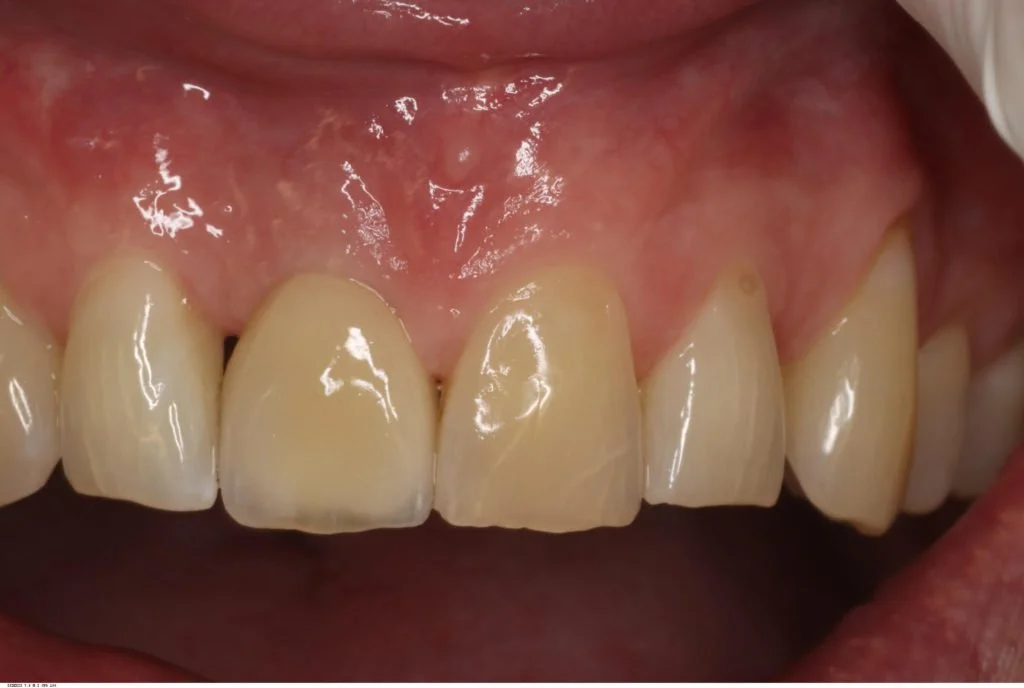

Patient Presentation

This healthy 40 year old patient presented with dull pain originating from vital tooth 11, which had a history of trauma. He had a very high smile line, making this an aesthetically critical case. This patient was a non-smoking individual with no medical contra-indications to minor oral surgery.

Due to the patient’s thin biotype, and very little existing labial plate seen on the cone beam radiograph, this treatment was carried out as a delayed two stage procedure. Therefore, the tooth was extracted and a provisional partial denture provided until complete soft tissue healing had occurred eight weeks later. This follows the early placement protocol as described in the ITI study guides.